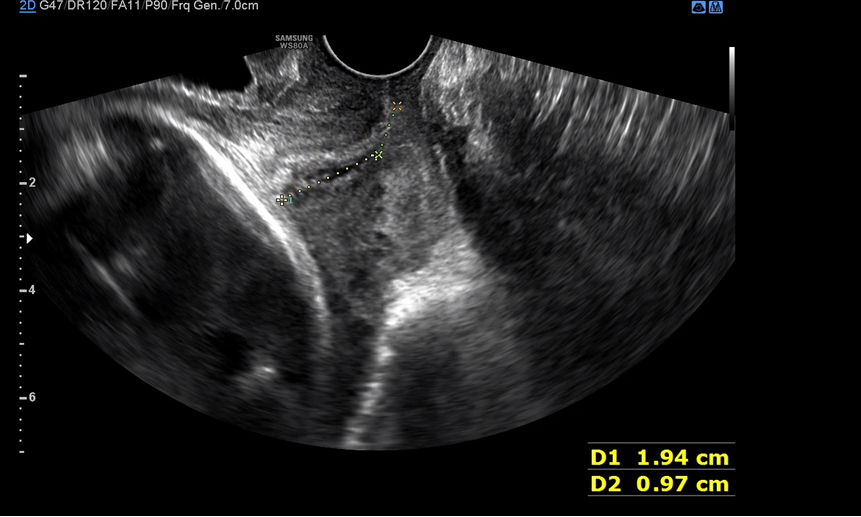

배 초음파를 마치고 질 균 검사를 하면서 자궁경부 길이도 다시 재주셨다. 지난번엔 자궁경부 길이가 오히려 좀 남는다고 하셨는데 이번엔 꽤 내려와 있었다. 입원하거나 너무 걱정할 정도로 내려온 건 아니고 지금쯤 이 정도는 내려와야 분만할 수 있다고 그러셨다. 배뭉침도 이 시기는 너무 없어도 분만이 어려울 수 있다고 지금 느끼는 불편함과 통증은 자연스러운 거라고 안심시켜주셨다. 그래도 피 비침이 있으면 바로 병원에 와야 한다고 말씀하셨던 거 같다. 이제 다음 진료는 37주 차에 방문하게 되는데 임산부로서 진료 보는 날이 이제 얼마 남지 않았다. 남은 기간 동안 조금 더 마음을 내려놓고 편히 지내도록 노력할까 한다.